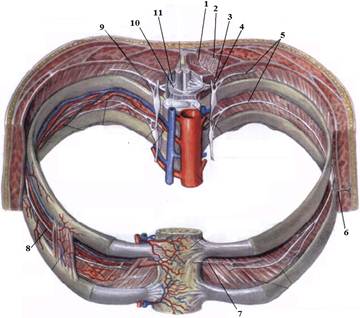

1. Яким номером позначено N. thoracicus?

2. Яким номером позначено N. intercostalis?

3. Яким номером позначено R. cutaneus lateralis?

4. Яким номером позначено R. dorsalis n. thoracici?

5. Яким номером позначено R. cutaneus lateralis r.dorsalis n. thoracici?

6. Яким номером позначено R. cutaneus medialis r.dorsalis n. thoracici?

7. Яким номером позначено R. cutaneus anterior?

8. Яким номером позначено Rr.communicantes n. thoracici?

9. Яким номером позначено Radix dorsalis n. thoracici?

10. Яким номером позначено Radix ventralis n. thoracici?

На таблицях і трупах студенти знаходять судинно-нервового пучка міжребрового проміжку. Далі на трупі розглядають хід і розподіл грудних нервів та ділянки їх інервації, Користуючись таблицями вивчають лімфатичні судини і вузли грудної клітки. На трупі ззаду і справа від грудної аорти знаходять грудну протоку. Визначають її корені хід топографію. На таблицях вивчають корені правої лімфатичної протоки визначають ділянки відпливу до двох головних лімфатичних проток.Викладач консультує студентів по темі заняття, показує незрозумілі деталі будови. В кінці заняття викладач шляхом тестування кінцевого рівня знань та вмінь оцінює роботу кожного студента в академічному журналі.